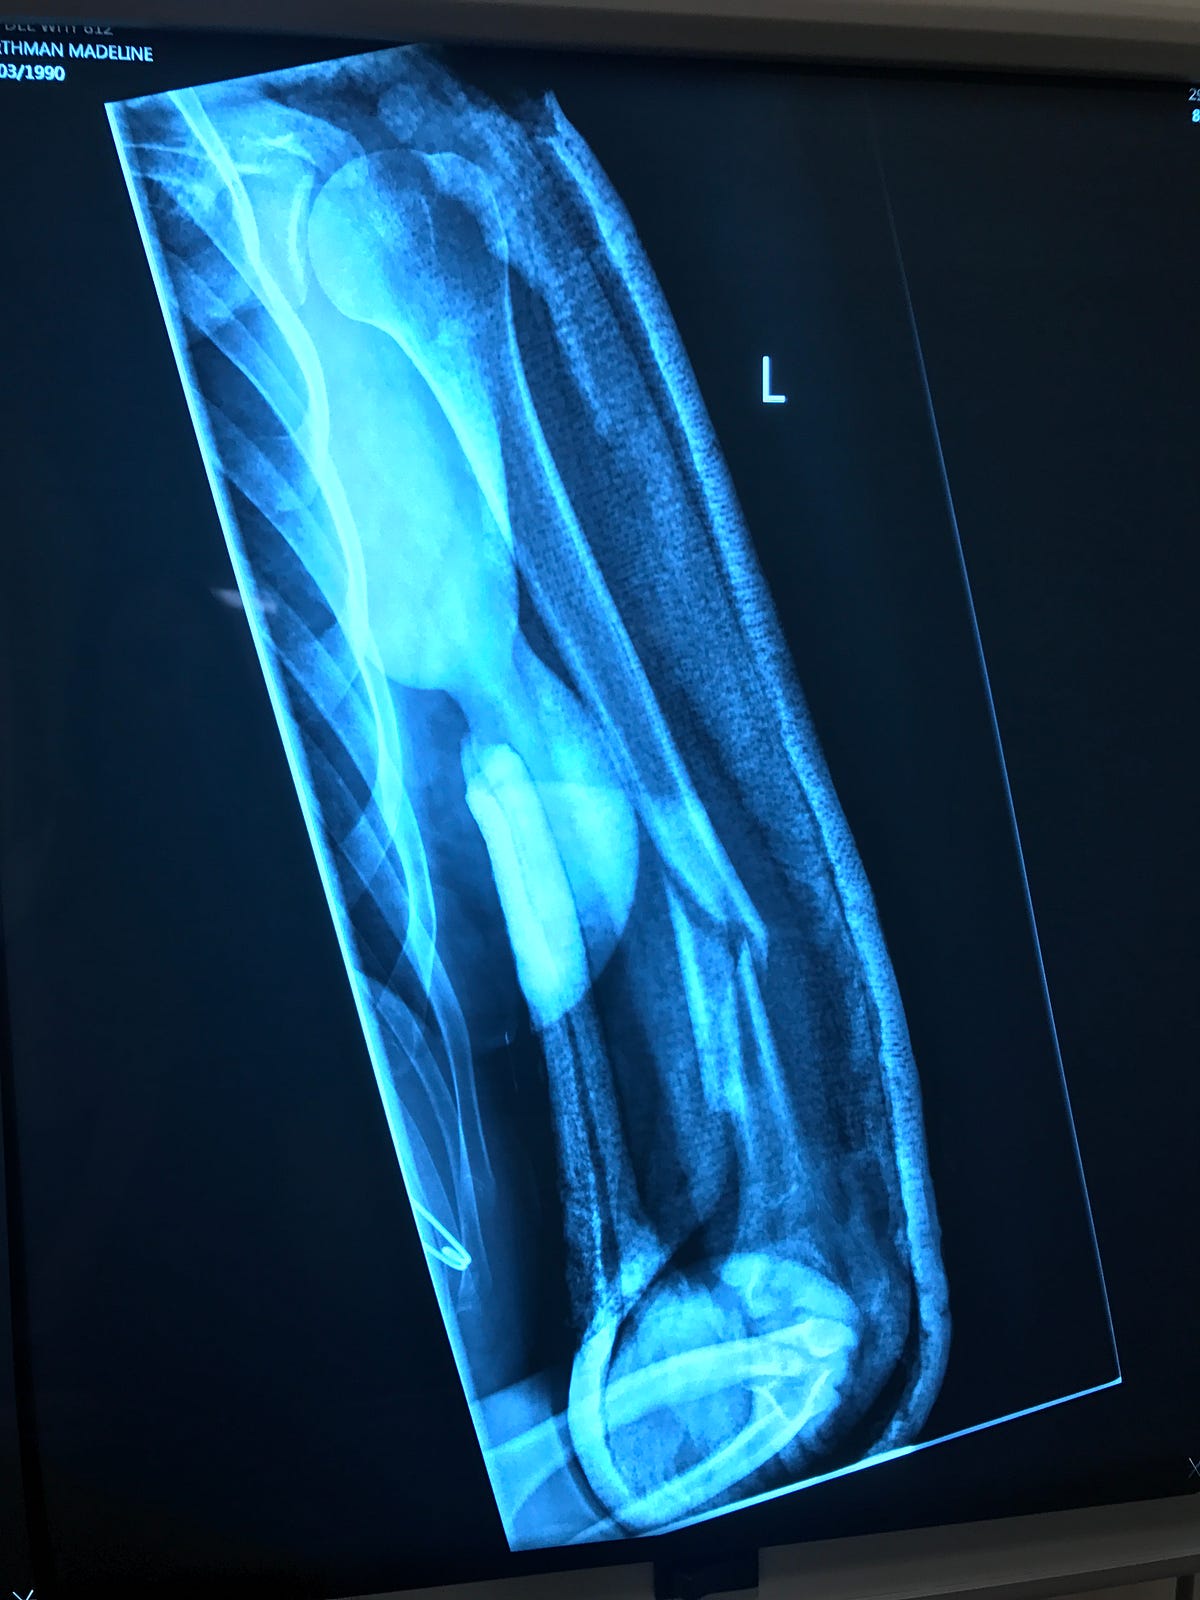

A Broken Humerus — Road to Recovery Maddie Wirthman Medium How To Shower With A Broken Humerus I recently fractured my left humerus and found that reading humerus fracture recovery blogs has been helpful in anticipating the healing process. There are two main approaches that your surgeon may use: During the first four weeks it is. In this video the surgeons discuss shoulder fractures. Shampoo and conditioner in basket at. They discuss the mechanism of injury, the.. How To Shower With A Broken Humerus.